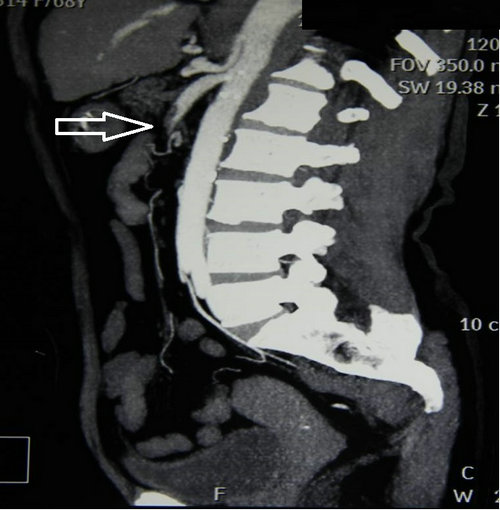

尚老太太今年84岁高寿, 1天前吃了个橙子后,突然出现腹痛、腹泻症状,被子女连夜送到郑大五附院消化内科。王长武副主任医师立即进行检查,在排除了急性胰腺炎、阑尾炎、胃肠炎后,当机立断做了腹部动脉CTA,结果发现肠系膜上动脉堵了,立即请血管外科医师会诊,急转该科。王兵副院长、崔文军副主任指导值班医生马上完善术前检查,紧急进行手术。

由于患者年龄大,冠心病、房颤20多年,基础情况差,术前请心内科关李华副主任及手术室闵娜医师前来会诊,给予制定围手术期处理意见。手术麻醉由胡强夫主任亲自进行,王兵副院长主刀。手术开始后发现肠管已经缺血发绀,幸运的是诊治及时,还未出现坏死迹象,腹腔也没有腹水。将肠系膜上动脉游离出来,取栓管取出的血栓将近10cm。缝合血管恢复血流后,肠管立即恢复红润,蠕动也明显改善。

急性肠系膜上动脉栓塞是由于栓子进入肠系膜上动脉造成阻塞所致,发病凶险,死亡率极高,最高可达88%—98%,症状表现为“Bergan三联征”:①突发腹部剧烈疼痛,药物不能缓解,早期腹软不胀,肠鸣音活跃,症状与体征不符;②器质性或并发房颤的心脏病,如房颤、风湿性心脏病、感染性心内膜炎、近期心梗病人;③胃排空障碍表现如腹泻、血便。该病的诊断非常困难,误诊率高达90%—95%,往往以阑尾炎、急性胃肠炎等疾病误诊,耽误了最佳治疗时间。肠管对缺血的耐受时间约12小时,尽早确诊并手术是降低死亡率的关键,患者肠道还有修复的可能性。缺血时间过长的患者肠道坏死,大量的肠毒素吸收、大量液体渗出导致患者很快出现中毒性休克,严重威胁生命。手术需要将肠道切除,导致“短肠综合征”。这类病人由于缺乏足够的肠管吸收营养,需要支付高额的全静脉营养费用,严重影响患者的生活质量。